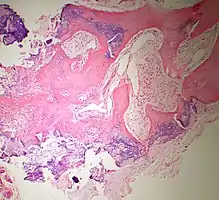

Histopathology

Bone Bizzare Parosteal Osteochondromatous Proliferation